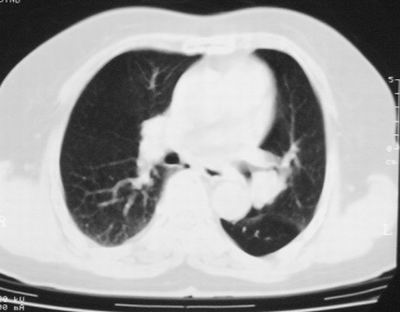

患者,女,64岁,4年前左腮腺"多形性"腺瘤手术治疗史.现复查胸部ct见左下肺块状影,该影与原左腮腺手术是否有联系?

本次复查胸部ct

左下肺癌伴左肺门淋巴结转移

支持考虑左下肺原发性肺癌,并左肺门淋巴结肿大

左下周围型肺癌伴左肺门淋巴结及右肺转移可能性大.